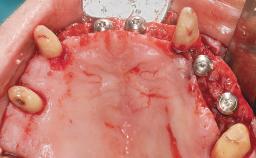

A 35-year-old Caucasian female presenting with advanced periodontal disease involving both the maxillary and the mandibular dentition was referred for evaluation. The patient, a non-smoker in good general health, requested treatment for recurrent periodontal abscesses, tooth mobility, and discomfort during chewing, as well as restoration of her missing teeth with a fixed prosthesis to improve mastication and esthetics. All residual maxillary teeth exhibited plaque deposits, deep pockets, bleeding on probing, and class III mobility and were evaluated as hopeless. All residual mandibular teeth except tooth 37 could be maintained after periodontal therapy.

| # of Implants | 8 |

| Bone Augmentation | Horizontal|Staged|Vertical |

| Augmentation Materials | Autogenous block(s) |